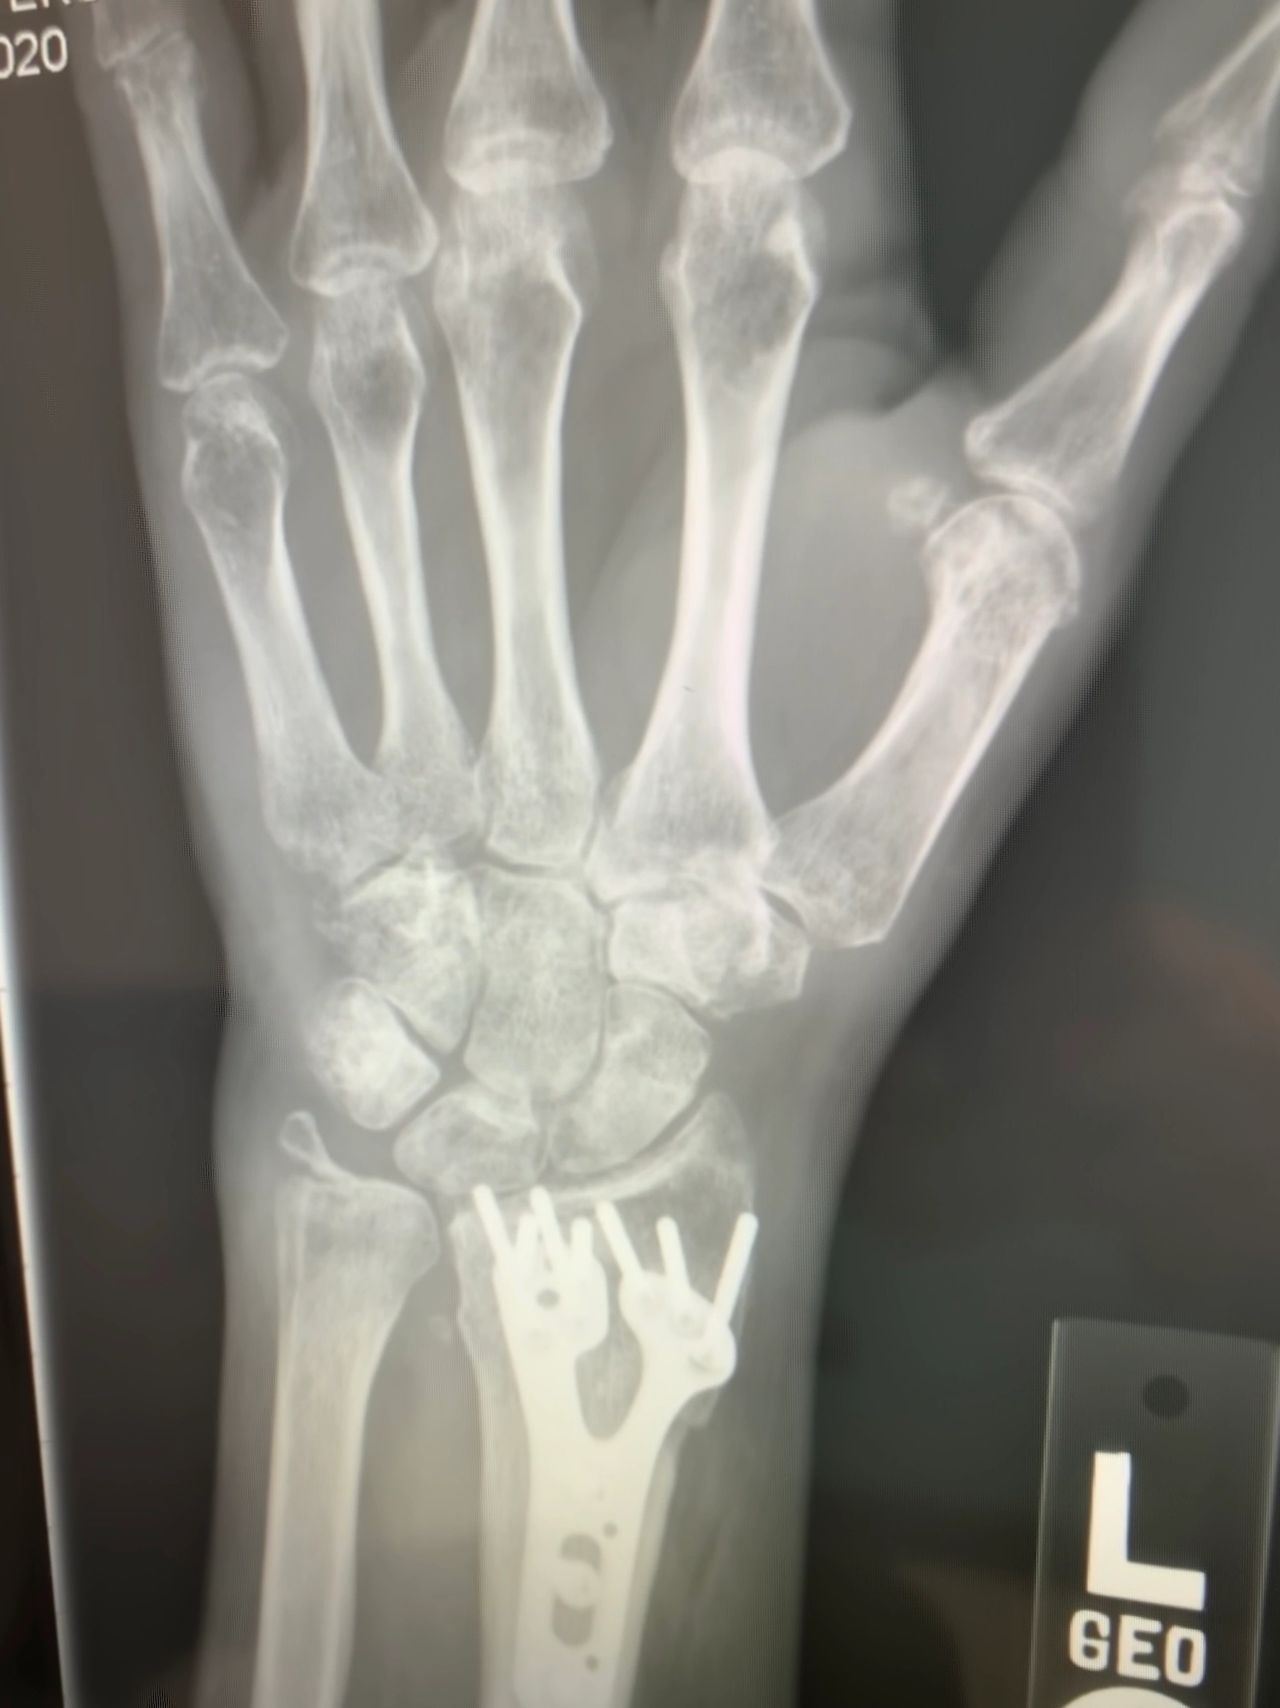

On May 20th, 2019, I met up with friends to play tennis. I had played at least weekly for a year, but it was hit or miss lately; coming off the medications and increased pain was exhausting. I needed socialization and competitive endorphins to give me a boost. We were finishing up a game when someone suggested playing longer. I hesitated a second, but my competitiveness pushed on. I went for an overhead hit at the baseline, took too many steps back, and fell on my left hand onto the racquet. The force caused my wrist into the palm of my hand, a definite fracture. My hand and wrist were in a deformed configuration. I was in shock with adrenaline as I continued to pick up the ball and walk over to my bag. My friends were also shocked and expressed the immediate need to be taken to the hospital. On route, reality and pain set in. An x-ray confirmed the obvious. It was set in place and then sent to a hand surgeon. Two days later, surgery to stabilize the radius fracture with a plate and screws. After two weeks in a surgical cast, sutures were removed into a fiberglass cast for four weeks. The fiberglass cast was removed, then onto physical therapy. I rehabilitated great, except my emotional state was maxed out.

I flew home two days later in an enormous heavy surgical cast, fixed straight and as big as my leg. I established a good relationship with my hand surgeon instead of flying back to Rochester for my 2-week post-op. Dr. Chan agreed to take the x-rays and remove the cast and sutures for Dr. O’Driscoll. At the same appointment, we discussed the removal of the wrist hardware. The friction of the metal was causing irritation to a tendon that made my middle finger stick, called a trigger finger. He injected a steroid for the inflammation. The surgery would be scheduled at a future date to allow the other arm to heal. One hand at a time.